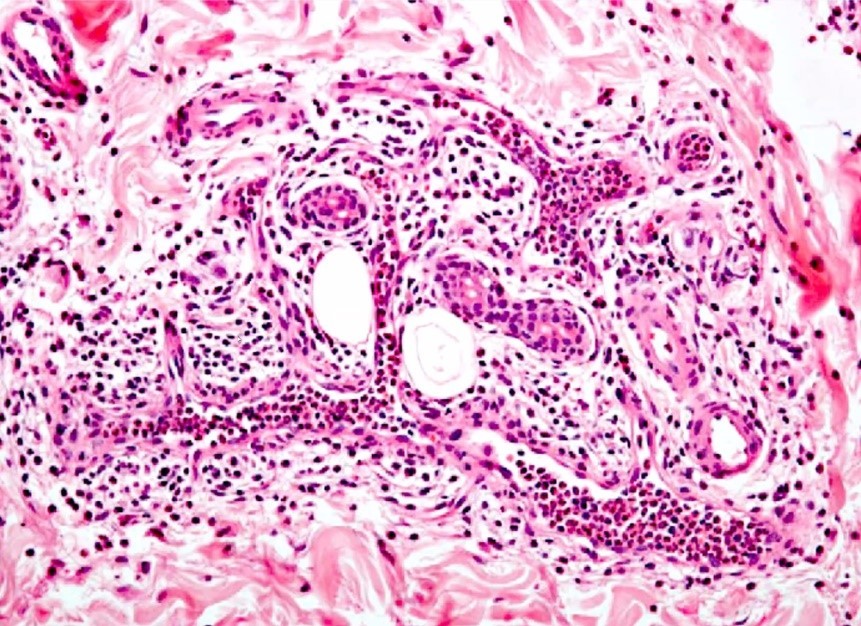

Vad visar bilden?

Granulomatös inflammation